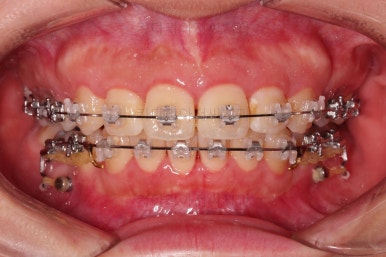

교합, 과개교합 모두 좋아졌고요.

발치 공간도 깔끔하게 닫히고 종료했습니다.

이제 부산무턱교정치과 전후 비교해 볼게요.

웃을 때 튀어나와 보이던 앞니도 많이 개선디ㅗ었고, 치열도 매우 예뻐졌습니다.